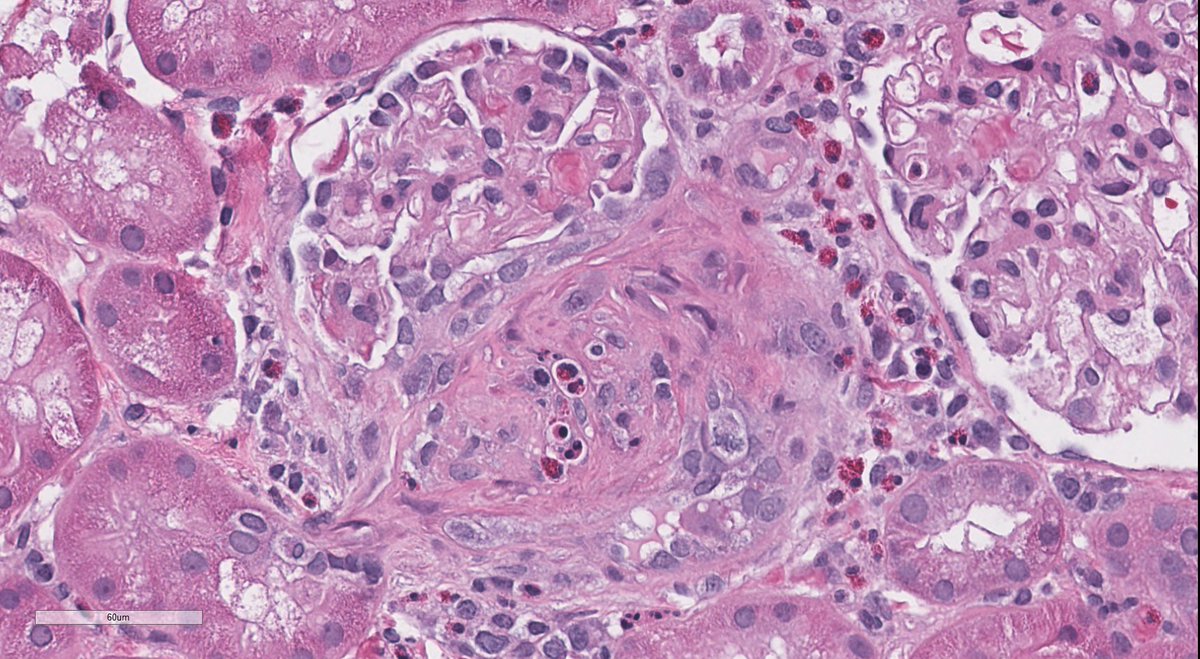

A simple classic case, because if you need to know something for path and nephrology boards in renal path, you need to know about PLA2R positive membranous. It was a game changer. For patient care too. It all started here nejm.org/doi/full/10.10…

MessiasNidia's tweet image. A simple classic case, because if you need to know something for path and nephrology boards in renal path, you need to know about PLA2R positive membranous. It was a game changer. For patient care too.  It all started here nejm.org/doi/full/10.10…